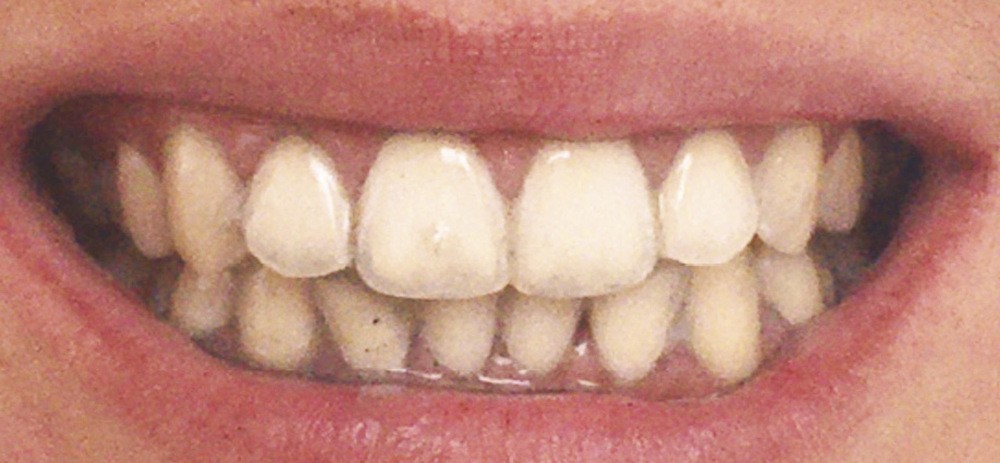

Les modifications hormonales à mettre en relation avec l’hygiène bucco-dentaire, les paramètres socio-économiques, l’âge précoce de la grossesse ainsi que l’augmentation du grignotage pourraient augmenter la prévalence des caries dentaires chez la femme enceinte. Ces patientes sont régulièrement sujettes à des envies multipliant le nombre de prises alimentaires souvent très riches en sucre. Ces apports sucrés, associés à la baisse du pH salivaire lors de la grossesse, entraînent un déséquilibre du cycle déminéralisation et de reminéralisation. Le risque carieux peut être augmenté, ainsi que la susceptibilité à l’érosion dentaire accrue par les vomissements et/ou les reflux gastro-œsophagiens [2]. L’action hormonale peut également avoir des répercussions sur les tissus parodontaux. La gingivite gravidique observée sur plus d’une femme enceinte sur deux, constitue une réponse inflammatoire de la gencive exacerbée par la présence de plaque bactérienne, et favorisée par l’augmentation des taux d’œstrogène et de progestérone [3] (fig. 1). 5 % des futures mères développeront un épulis, dont l’étiologie reste méconnue (fig. 2) [4].